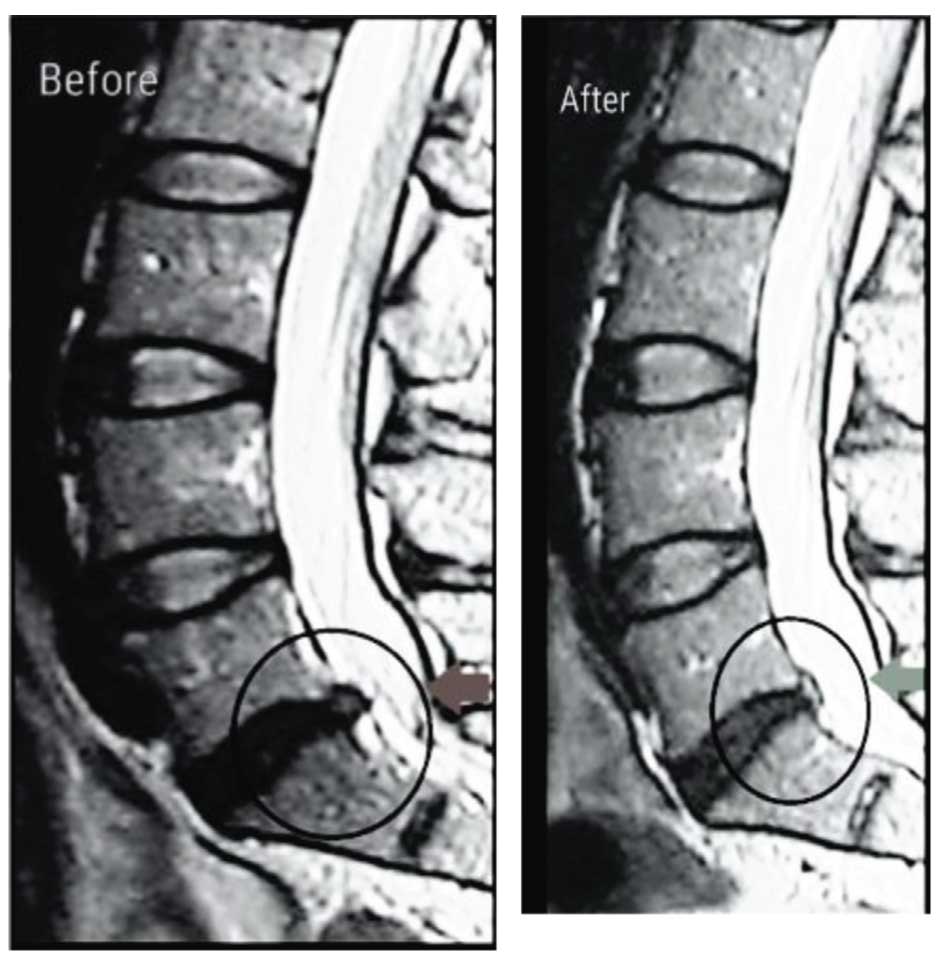

There were improvements of disc height in 27 (72.97%) patients, ranging from 1.1 up to 5.3 mm,with a mean of 2.31±1.24 mm. LBP was improved in 29 (74.36%) patients while radicular pain improved in 33 (84.61%) patients; disc height improved in 27 (72.97%) patients.

There were improvements of disc height in four (11.76%) patients, ranging from 0.1 up to 0.3 mm, with a mean of 0.043±0.091 mm. LBP was improved in 25 (73.53%) patients while radicular pain improved in seven (20.59%) patients; disc height improved in four (11.76%) patients. When we compared both groups, we found that there were nonsignificant differences in the improvement of LBP and a highly significant difference in the improvement of radicular pain and disc height between both groups (Figs 1–4 and Tables 1–4).

Discogenic pain is a major problem in the lumbar area, and it may be caused by progressive annular breakdown and tearing, which cause pain by stimulating pain fibers in the outer one-third of the annulus and by compression over the nerves’ roots. Spinal decompression systems using the DRX9000® have become a noninvasive intervention for the treatment of LBP caused by disc protrusion or herniation by expanding the intervertebral space and reducing the disc protrusion. Our study showed that there was an improvement in back pain and lower extremities’ radicular pain with the decompression system; the improvement was more significant in lower extremities’ pain than back pain.

Figure 1

There was a significant improvement in the disc heights of the majority of patients by the decompression system. Comparing with the control group, we found highly significant improvement in patients treated with the decompression system with regard to radicular pain and disc height compared with other physiotherapy modalities. Our study was in agreement with Richmond et al. [7] who stated that Non-surgical Spinal Decompression.